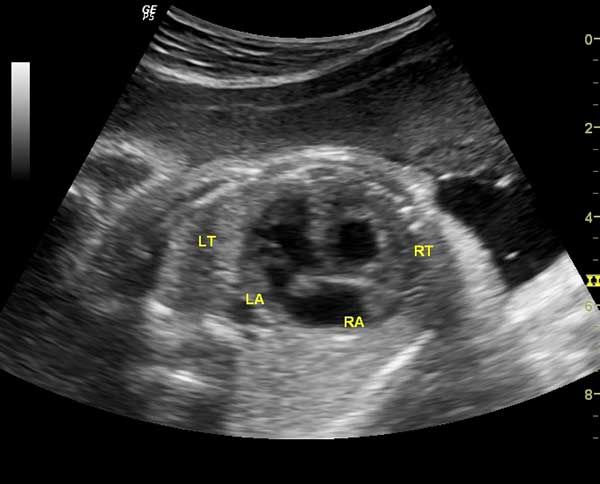

This young lady has abdominal pain and chest discomfort.She was undergoing treatment for infertility.What is your diagnosis?